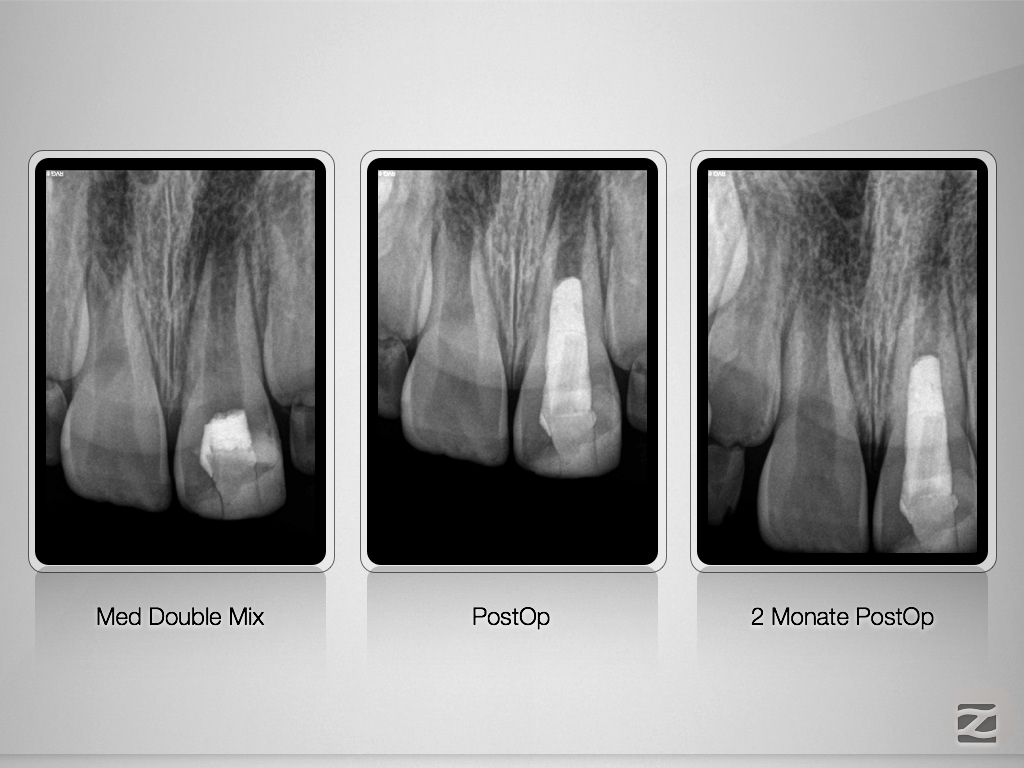

Chance Pulpotomie